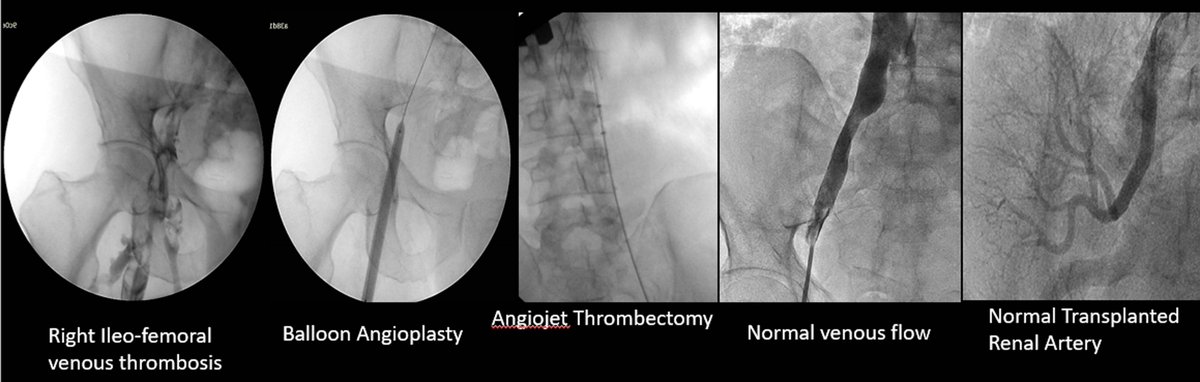

Case 62: with @BhaveshPopat7 . Right lower limb acute extensive iliofem DVT; pharmacomechanical thrombectomy with Angiojet; images below 👇 . #MedTwitter #meded #hematology @SIRRFS @SIR_ECS @SIRspecialists @nihardesai7

@DrRajeshVijay

Rajesh VIJAYVERGIYA

3 years

2

5

20